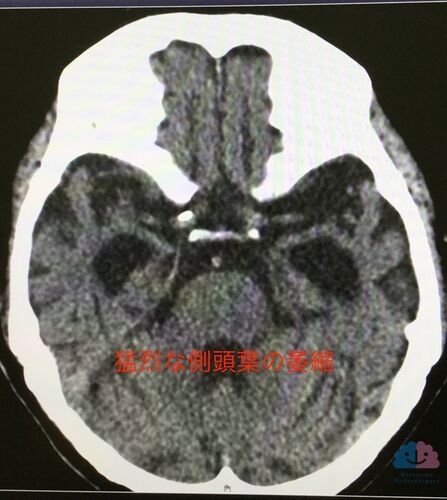

病型診断だけでは片手落ち。